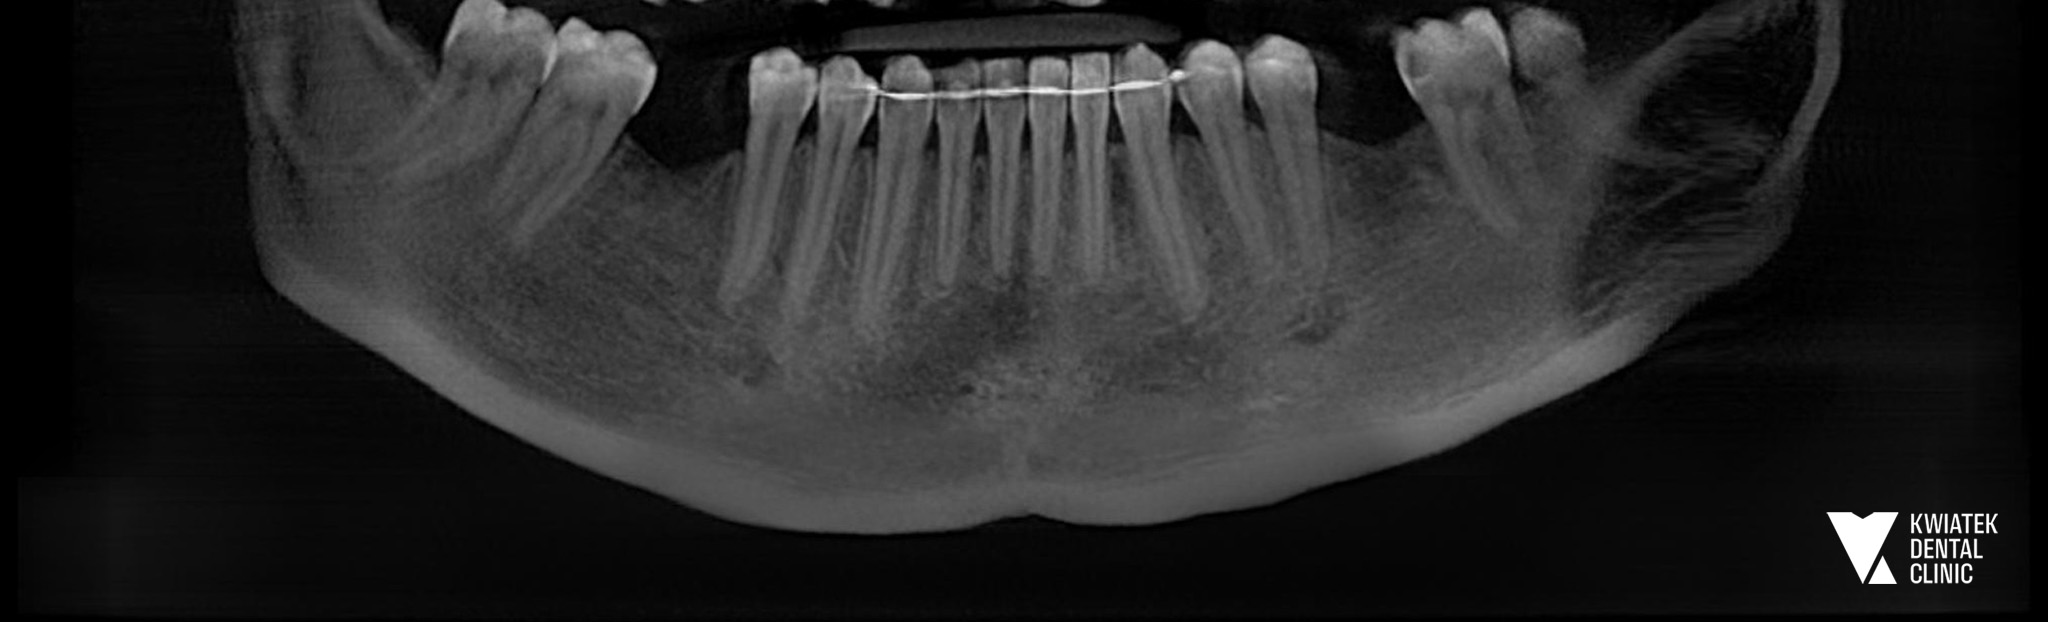

PRZED

Pacjentka zgłosiła się do naszej kliniki z problemem braków zębowych w odcinkach bocznych żuchwy. Braki te dotyczyły pierwszych zębów trzonowych, czyli tzw. zębów szóstych. Warto podkreślić, że to właśnie one najczęściej są tracone jako pierwsze. Wynika to z faktu, że są pierwszymi stałymi zębami trzonowymi pojawiającymi się w jamie ustnej, zwykle już około szóstego roku życia, przez co przez wiele lat poddawane są największym obciążeniom podczas żucia.

Proces leczenia rozpoczął się od szczegółowej diagnostyki stomatologicznej oraz analizy stanu jamy ustnej. Wykonano badania radiologiczne, dokumentację fotograficzną oraz skan wewnątrzustny, który umożliwił cyfrowe zaplanowanie leczenia implantologicznego.

Na podstawie diagnostyki stwierdzono brak zębów 36 oraz 46 w żuchwie. Już wcześniej, podczas wcześniejszych wizyt, zaproponowano Pacjentce odbudowę tych braków przy użyciu implantów, jako najbardziej przewidywalnej i trwałej metody leczenia.